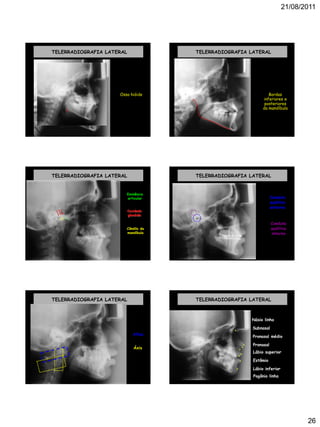

TELERRADIOGRAFIA LATERAL

Osso hióide

Bordas

inferiores e

posteriores

da mandíbula

Eminência

articular

Cavidade

glenóide

Côndilo da

mandíbula

Conduto

auditivo

interno

externo

Atlas

Áxis

Násio linha

. Subnasal

.

Pogônio linha

Pronasal médio

. Pronasal.

Lábio superior.

Estômio

Lábio inferior